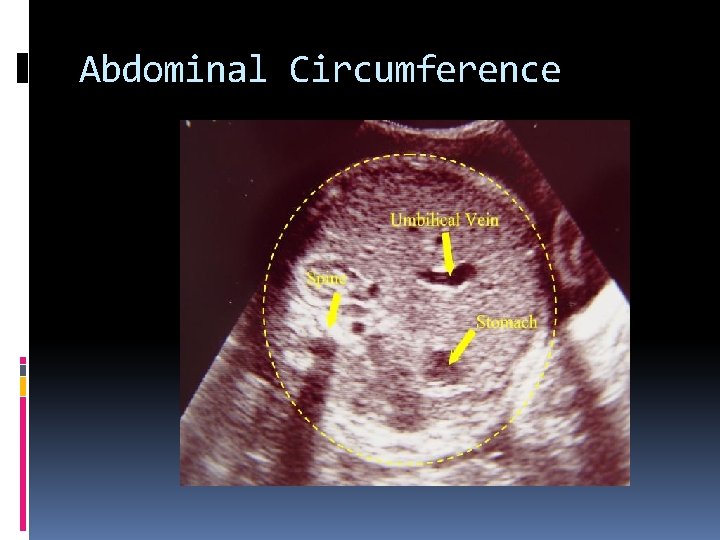

AC Abdominal Circumference Measured at the level of the portal vein and stomach Circumference measurements –both ellipse and linear- should include soft tissue. The least reliable in establishing gestational are due to significant genetic and physiologic variations in size After 25 weeks.

Abdominal Circumference

Anatomy that must be seen in the Abdominal Circumference The Abdominal Circumference must include the portal section from the umbilical vein, the stomach and a true cross section of the spine with 3 ossification centers. It should be circular in shape.